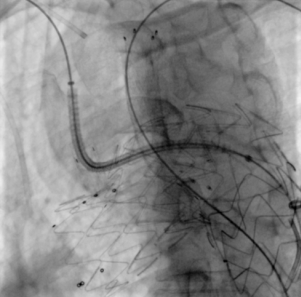

术后造影

术后造影显示,支架有效隔绝瘤腔,LCCA、LSA和ARSA血流供应通畅,支架无移位和内漏现象发生,手术圆满成功。

治疗车怎么推【弓部重建直通车】梅州市人民医院心内科团队运用Castor®分支型支架联合预开窗技术治疗主动脉弓动脉瘤合并迷走右锁骨下动_https://www.jmylbn.com_新闻资讯_第17张

术后造影(正位)

治疗车怎么推【弓部重建直通车】梅州市人民医院心内科团队运用Castor®分支型支架联合预开窗技术治疗主动脉弓动脉瘤合并迷走右锁骨下动_https://www.jmylbn.com_新闻资讯_第18张

术后造影(左前斜)